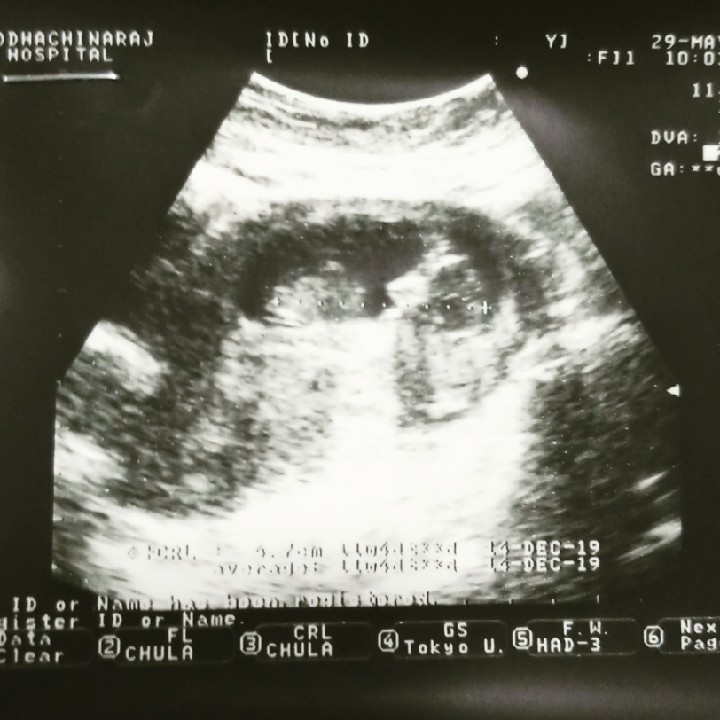

ชัดจ้า ซาวตอน 12w6d